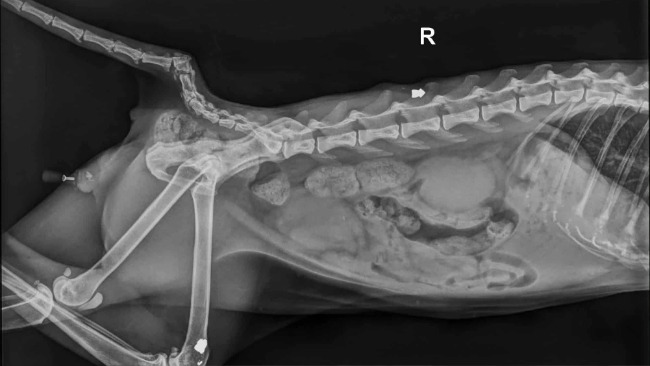

– RTG wykazało, że ktoś… strzelał do niego – Max nosi w sobie kilka śrutów.